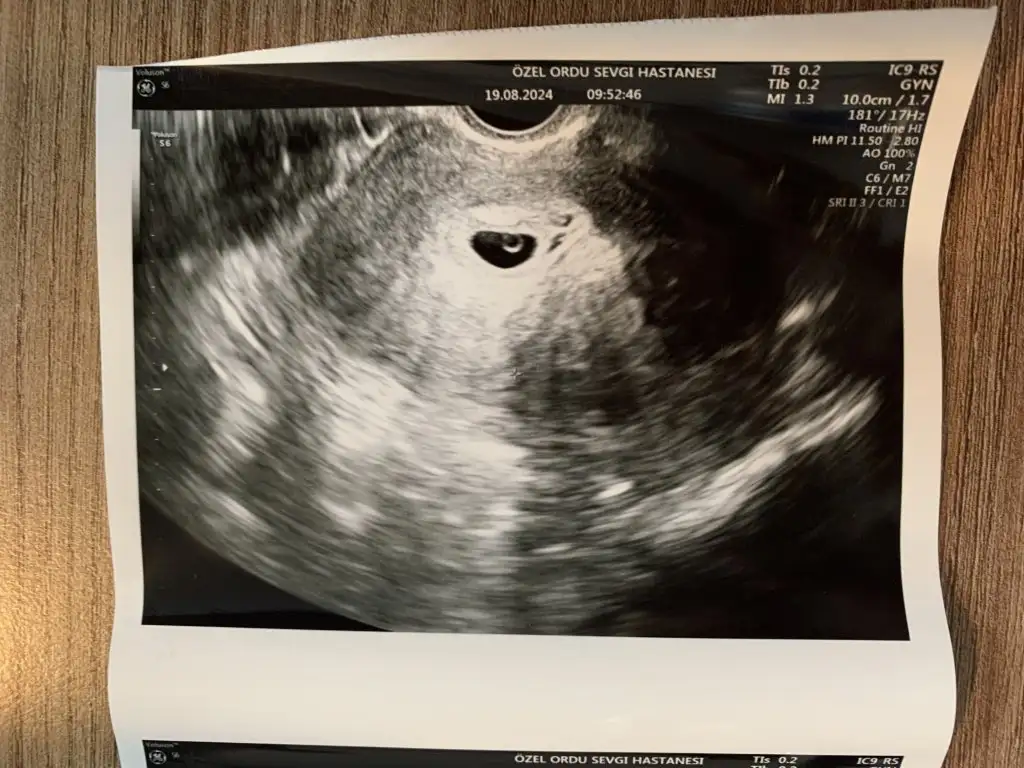

Seninle günümüz tamı tamına aynı benim de son adetim sekiz temmuzdu ayın yirmi beşi transfer tarihi benim üçüncü gün embriyosu benimde bugün 6+2 olmam gerekiyordu sen kalp atışını gördün mü ultrasonda kese görüntümü aldım ama büyüklüğünü vs anlamadım

Evet dün kalp atışını gördüm ve kısa dinletti doktorum. 3 hafta sonra tekrar gel dedi. Kese görüntüsü olan ultrason fotosunu at istersen büyüklüğünü söyleyeyim sana. Ya da atmak istemezsen kenardaki sebillerde CRL yazar, onun karşısındaki rakam kese boyutunu gösterir bi incele bakalım

Hayırlı olsun bence erken bile duymuşsun herşey yolunda gözüküyor Allahın izniyle dur atıyorum terimleri anlamadım daha acemiyim seninkiyle kıyasla bakalım nasılım acaba:))

Eklentiler

• IMG_4823.webp

IMG_4823.webp

56,4 KB · Görüntüleme: 180

Bu benimki.